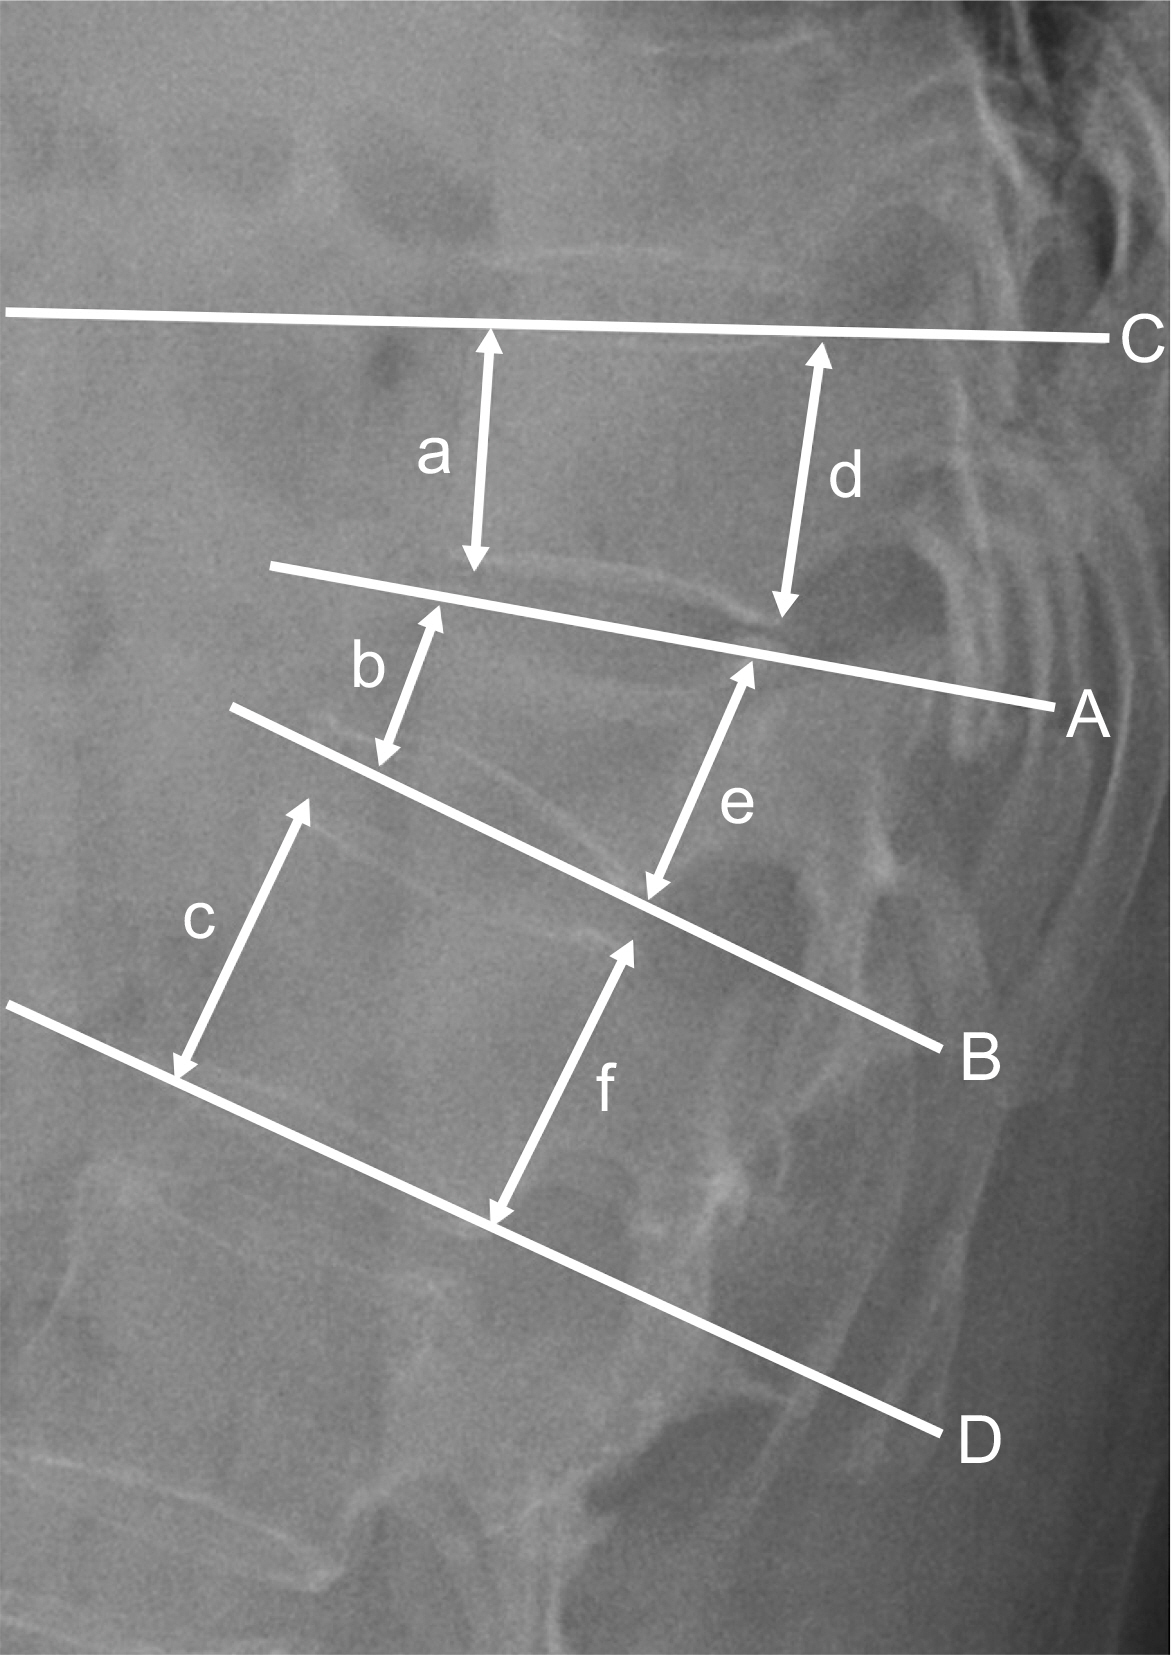

Fig. 1.

Radiography showing linear and angular measurement. Wedge angle (∠AB°), local kyphotic angle (∠CD°), anterior body height (200× b/(a+c) %), posterior body height (200×e/(d+f) %).

Values are presented as mean ± standard deviation. Refer to Fig. 1 for the measurement of anteroposterior body height. CPF: conventional posterior fixation, PPSF: percutaneous pedicle screw fixation.